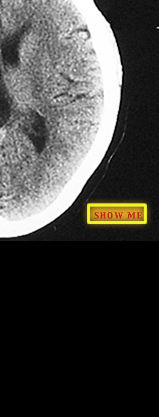

Can you identify the area of his brain that was affected?